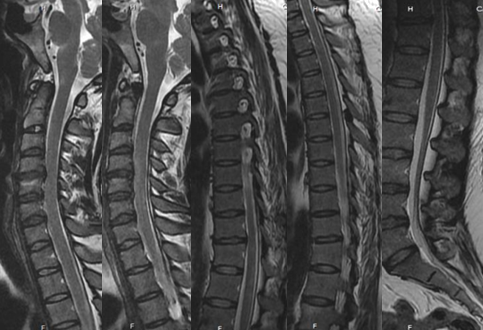

脊髓出血发病急,临床少见,血管畸形是脊髓出血的主要原因。主要表现为剧烈胸腰背部疼痛及截瘫,感觉障碍及括约肌功能障碍。脊髓出血与急性脊髓炎、脊髓梗死相互鉴别。脊髓炎发病前可有呼吸道或消化道感染等诱因,神经根刺激症状不明显,MRI检查可见T2WI横贯性的异常高信号。脊髓梗死可急性或亚急性发病,多发生在中老年人,以脊髓前动脉梗塞多见,运动障碍明显,感觉障碍轻微或缺失,MRI检查T2WI像可见脊髓前动脉供血区高信号,后索多不受累。

患者女性,41岁,间歇性双下肢无力2月,小便费力1月。

答案:脊髓硬脊膜动静脉瘘(SDAVF)。SDAVF是最常见的脊髓血管畸形,多累及胸腰段,占脊髓血管畸形的70%。本病中老年男性多见,多缓慢起病,并进行性加重,少数呈急性起病,临床确诊较难。临床表现步态异常、下肢乏力、感觉障碍、疼痛,伴或不伴括约肌功能障碍等。症状不典型时可误诊为周围神经病等,如表现为单侧下肢无力。表现为双足袜套样感觉异常时会误诊为糖尿病周围神经病等。表现为下肢放射性疼痛时被误诊为退行性脊椎疾病。脊髓MRI:T1示肿胀的脊髓呈低信号影,伴有弥漫性增强; T2呈多节段脊髓中央部高信号(大白萝卜样);脊髓背侧多有环状低信号(提示扩张、扭曲的静脉血管,呈小黑芝麻样)。

患者81岁,男。 突发腰背部疼痛伴排尿困难18d、双下肢麻木无力1d。

答案:脊髓血管畸形-硬脊膜动静脉瘘。解析同上。